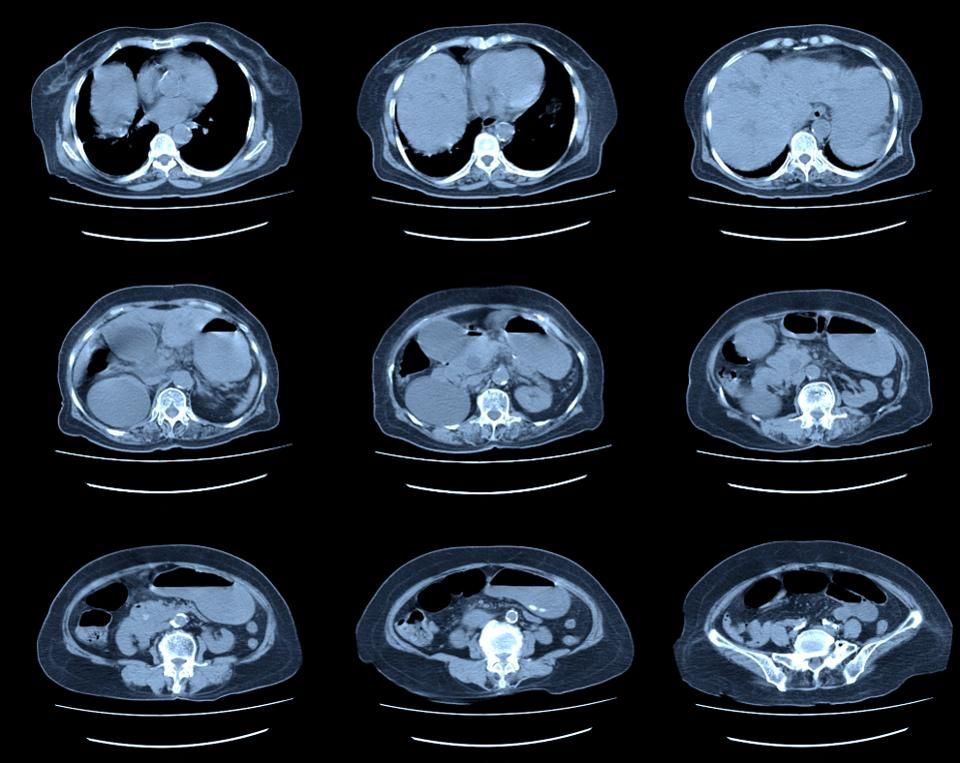

让我们首先看看关于肾癌的一些基本情况,最近几年,在美国肾癌的患者人数急剧攀升,从2001到2010年,肾癌的患者增长了20%。当然有一部分增长是源于美国人口的老龄化,和肥胖人群体的增加。但是最多的是因为接受CT 检查的人数增加了。人们由于这样或那样的原因接受了CT检查,检查中额外发现了肾脏有可疑的增生。

这几年,在美国的某些地方,接受CT检查的人数迅速增长,根据 达特茅斯学院的调查,从2010-2014年,密西根有一半享受医保的人,接受了胸或腹部的CT检查。相比之下,另外一个州,爱荷华周仅是三分之一。下面一张图片是美国各州CT检查普遍性的情况,颜色越深,CT检查的比率越高,弗罗里达位居榜首。

接受了CT扫描检查,医生发现了异常,一部分异常的确是非常严重的问题,需要马上治疗。还有一部分是顺便发现,也称作“意外瘤”,是否存在严重的风险哪?不确定!

比如一个患者,他的肾癌可能就是意外瘤。 因为与肾不相关的原因,所以接受了腹部CT检查,结果发现有肾上有一个1 厘米的增生,有两种处理方法: